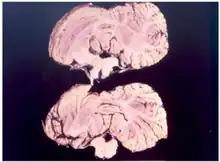

La maladie provoquée par l'accumulation de la protéine prion, ramollit les tissus du cerveau jusqu'à le rendre spongieux.